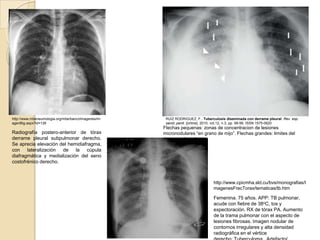

Radiografía postero-anterior de tórax

con derrame pleural izquierdo

http://www.mbeneumologia.org/mbe/bancoImagenes/im    RUIZ RODRIGUEZ, F.. Tuberculosis diseminada con derrame pleural. Rev. esp.

agenBig.aspx?id=126                                  sanid. penit. [online]. 2010, vol.12, n.3, pp. 99-99. ISSN 1575-0620

Flechas pequenas: zonas de concentracion de lesiones

Radiografía postero-anterior de tórax               micronodulares “en grano de mijo”. Flechas grandes: limites del

derrame pleural subpulmonar derecho.                derrame pleural.

Se aprecia elevación del hemidiafragma,

con lateralización de la cúpula

diafragmática y medialización del seno

costofrénico derecho.

http://www.cpicmha.sld.cu/bvs/monografias/I

magenesFrecTorax/tematicas/tb.htm

Femenina. 75 años. APP: TB pulmonar,

acude con fiebre de 38oC, tos y

expectoración. RX de tórax PA. Aumento

de la trama pulmonar con el aspecto de

lesiones fibrosas. Imagen nodular de

contornos irregulares y alta densidad

radiográfica en el vértice